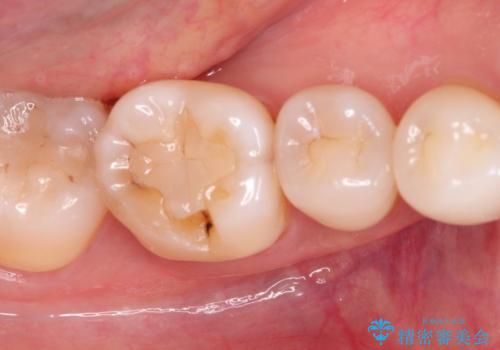

- 以前治療した歯が欠けたことを主訴に来院されました。

見た目もよく強度の高いものでの修復を希望されましたのでセラミックインレーにて修復しました。